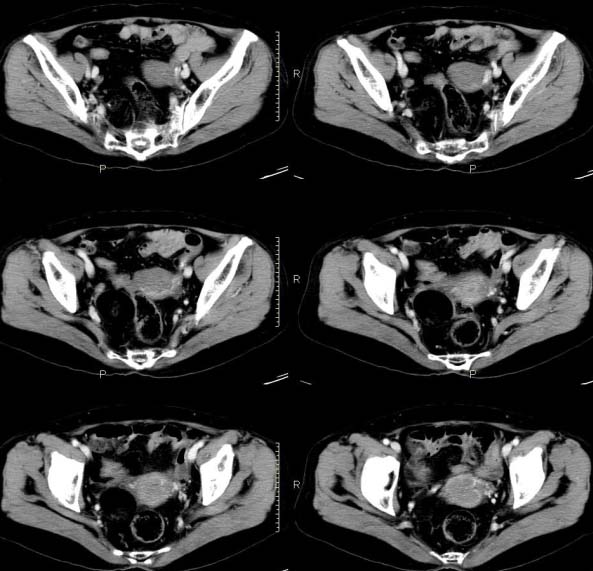

女,63岁,绝经15年,从阴道内有液体流出约1月余,且带有血,患者一般情况很差,在家属搀扶下行走。请大家看看是子宫病变还是宫颈病变?

宫腔有积液 但无软组织肿块 考虑炎性变

子宫颈体积增大,宫颈壁不均匀性增厚,且不均匀性强化。考虑为宫颈ca。

子宫颈内见低密度影,外形不规则,不均匀强化,考虑占位,子宫颈癌可能性大。